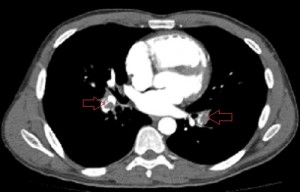

Axial images of CT angiogram of the pulmonary arteries 1 day after the patient’s admission showing filling defects in the central branches of both pulmonary arteries.